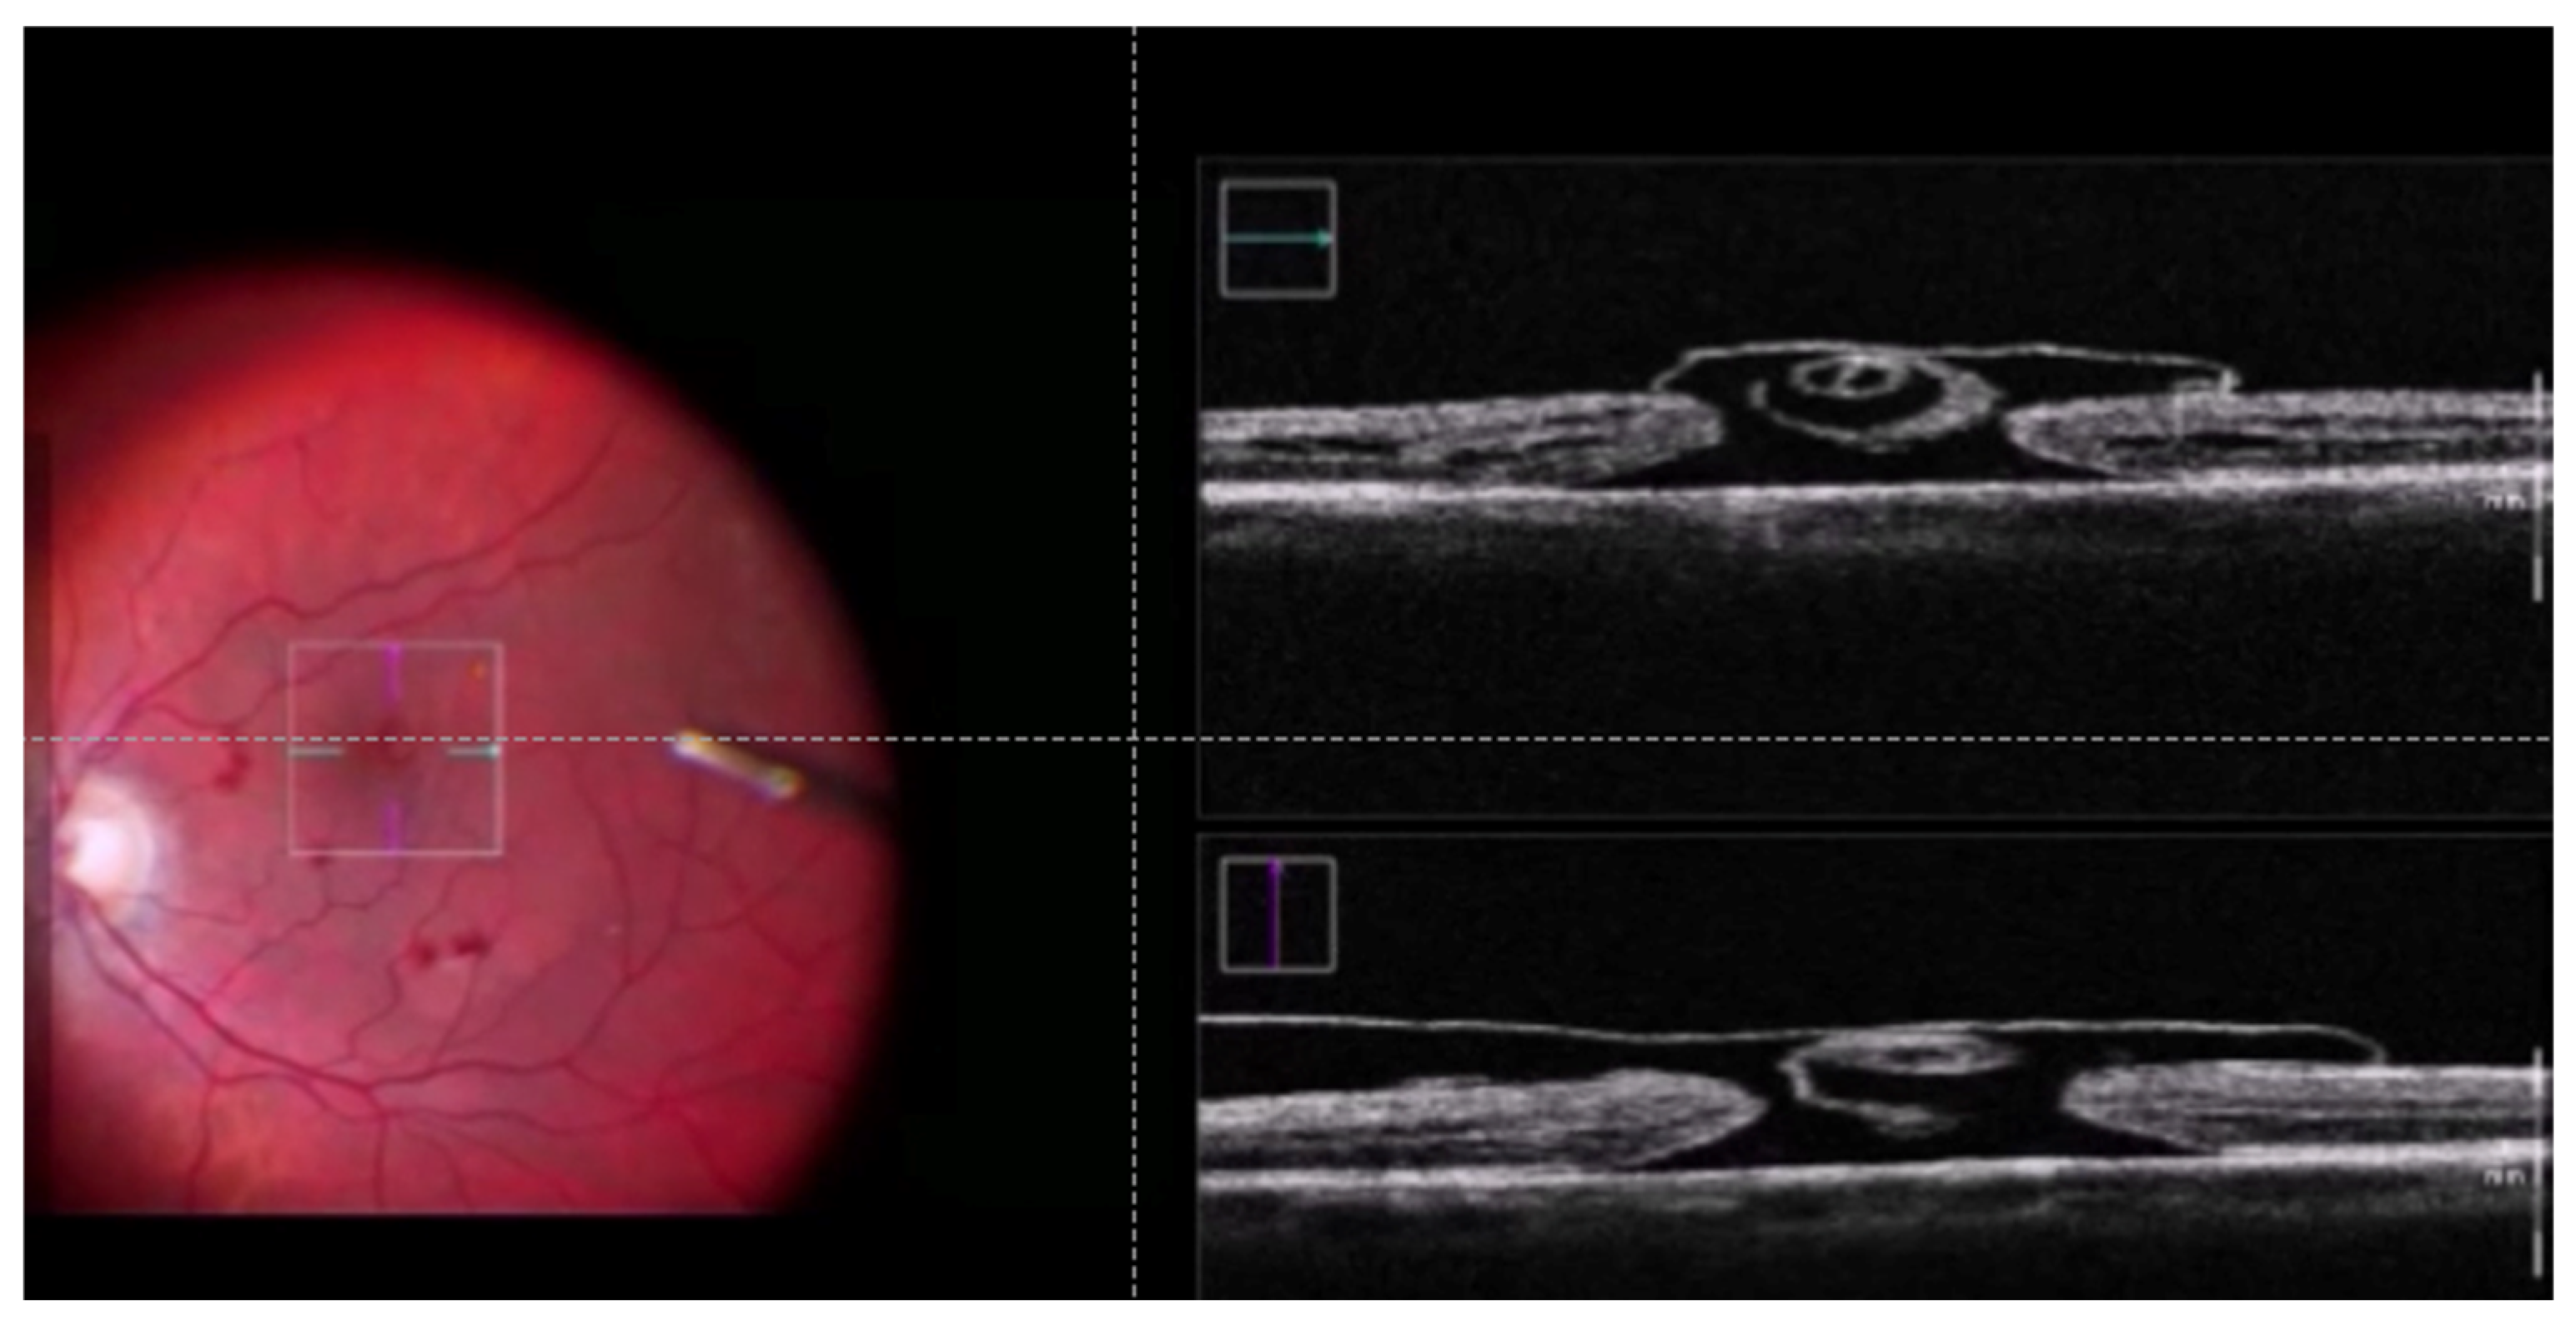

2. Materials and Methods

3. Results